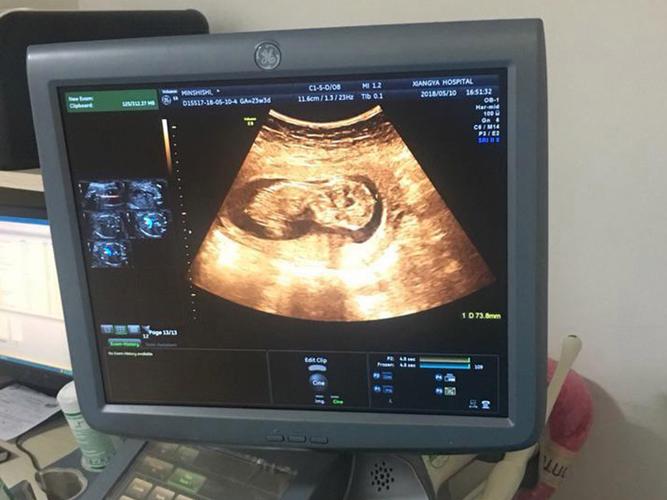

孕期13周NT检查是啥?-第2张图片-中州医学会

(图片来源网络,侵删)

NT检查是一种无创、无痛的检查,主要通过B超(超声波)来完成。

1. 过程:您需要平躺,医生会在您的腹部涂抹耦合剂,然后用B超探头在肚子上移动,清晰地观察胎儿的形态。

2. 测量:医生会找到标准的胎儿正中矢状切面,清晰地显示胎儿的鼻骨、鼻尖、前额和颈项,B超机会自动或手动测量胎儿颈后皮下液体的厚度,这个厚度就是NT值。

3. 时长:整个检查过程通常很快,大约需要15-30分钟,但有时胎儿位置不好可能需要更长时间或您走动一下后再做。